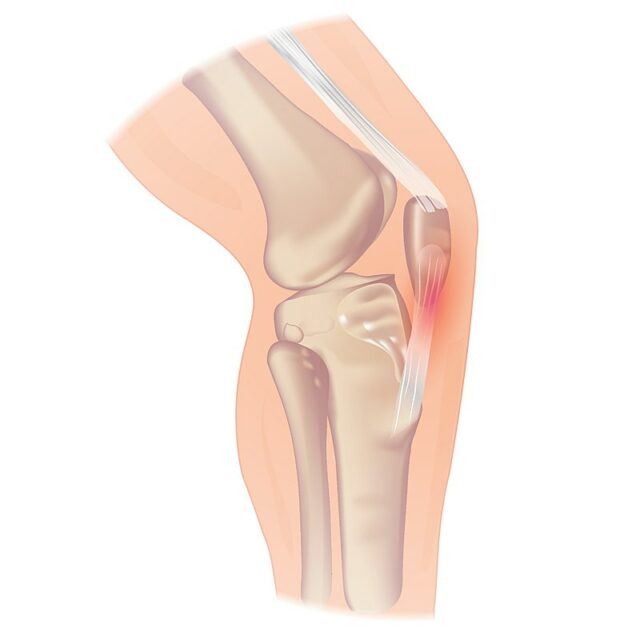

Aunque la tendinopatía rotuliana puede producirse en el polo inferior de la rótula, también puede producirse en la inserción del tendón en la tuberosidad tibial, lo que es más raro. Si un paciente refiere dolor en la base de la rótula, cabe sospechar una tendinopatía del cuádriceps.

Una prueba útil para confirmar la tendinopatía rotuliana es la prueba del hospital Royal London, que tiene una buena sensibilidad del 88% y una especificidad del 98% para diferenciar a los pacientes con tendinopatía rotuliana de otras fuentes de dolor anterior de rodilla.

Para realizar la prueba, palpe el tendón rotuliano en busca de sensibilidad de proximal a distal con la rodilla en extensión completa. A continuación, vuelva a palpar el punto sensible en 90 grados de flexión de la rodilla. La prueba es positiva si el dolor en posición flexionada es menor o inexistente.

En esta posición, también puede realizar directamente la prueba de Hoffa para ver si la almohadilla de grasa está implicada o no. El procedimiento es más o menos el mismo que para la prueba del hospital Royal London, sólo que se empieza en posición flexionada y ahora se palpa la almohadilla de grasa infrapatelar en busca de sensibilidad a izquierda y derecha del tendón rotuliano. Luego se palpa de nuevo con la rodilla estirada. Esta prueba también es positiva si el dolor en posición extendida es mayor que en posición flexionada.

Obsérvese que la irritación de la almohadilla adiposa suele presentarse con un dolor más difuso y suele agravarse con una sobreextensión de la rodilla. En los atletas jóvenes al inicio de la pubertad, tendrás que tener presentes las patologías del cartílago de crecimiento: La más común es la enfermedad de Osgood-Schlatter, una lesión por uso excesivo caracterizada por la osificación del hueso a lo largo del cartílago de crecimiento en el tubérculo tibial. En la versión más grave, Osgood Schlatter puede dar lugar a un cartílago de crecimiento de la tuberosidad tibial sin fusionar. Sinding Larsen Johannson es el equivalente a Osgood Schlatter, sólo que ahora está afectado el vértice de la rótula.